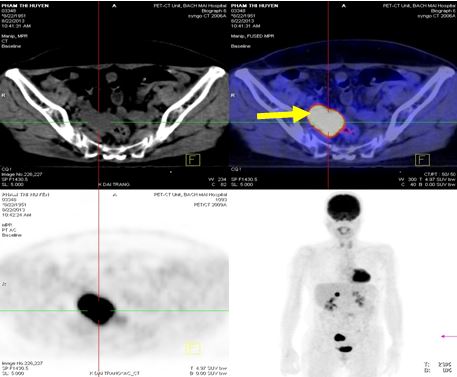

Chụp PET /CT đánh giá sau điều trị :

+ Không thấy hình ảnh tăng hấp thu và chuyển hoá FDG bất thường tại các vị trí trong cơ thể.

Hình 5. Hình chụp PET/CT: Khối tổn thương tại tuyến thượng thận phải đã tan biến

Hình 6. Hình chụp PET/CT: Khối tổn thương phúc mạc tại hố chậu phải đã tan biến